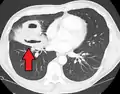

- Pulmonary abscess on CT scan

- A subpleural abscess.